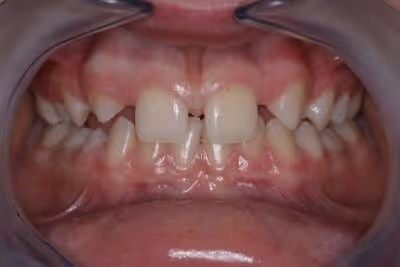

L'agénésie dentaire est une situation dentaire d’origine le plus souvent congénitale, relativement courante qui se caractérise par l'absence de certaines dents permanentes. Cela signifie que certaines dents n'apparaissent pas sur les arcades dentaires.

Cela provoque des problèmes d'alignement dentaire et par voie de conséquence, des problèmes d’occlusion.

Quand on constate la présence d’agénésies sur les arcades dentaires, les dents les plus couramment affectées sont les incisives latérales, les prémolaires, mais cela peut aussi concerner n’importe quelle dent.

L'agénésie dentaire peut être unilatérale, bilatérale ou se situer dans n’importe quelles zones de l’arcade dentaire supérieure ou inférieure

L'agénésie dentaire a toujours des conséquences importantes sur l'alignement dentaire et la fonction occlusale.

Lorsqu'une dent est absente, cela crée un espace sur l'arcade dentaire et si rien n’est fait du point de vue orthodontique, cela peut entraîner le déplacement des autres dents adjacentes vers cet espace vacant.

Cela provoque une mauvaise occlusion, des problèmes de mastication et une esthétique dentaire altérée.